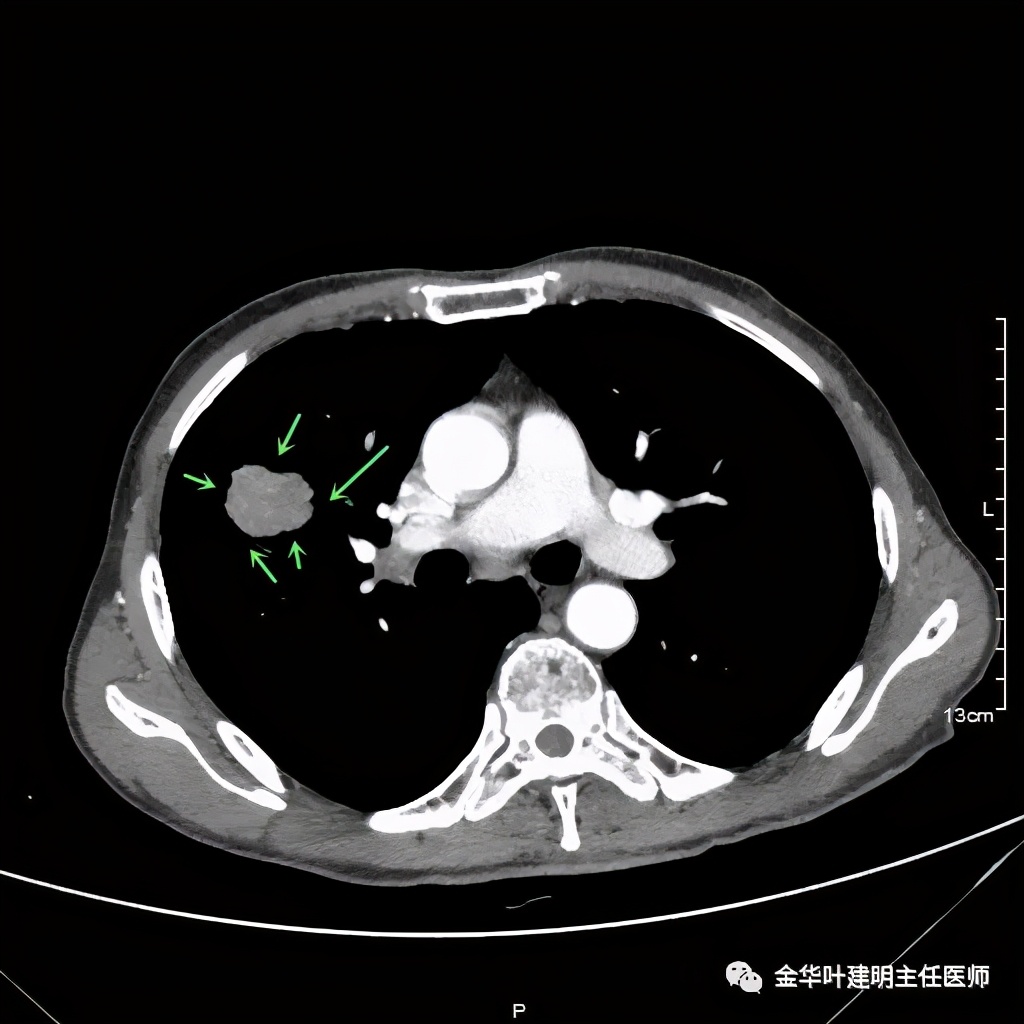

上图示病灶边缘不太光整,内部密度不太均匀

上图紫色箭头示叶间胸膜受牵拉,病灶边缘部分见到细毛刺

上图示纵隔窗病灶有膨胀性,内部有强化较明显的条索状(新生血管?)

上图示纵隔窗病灶表面欠平整,中间有小空洞,密度不均,局部似有坏死(空洞旁边)

上图紫色箭头示明显的叶间胸膜牵拉,红色箭头示病灶,中间还有空腔,边缘有细毛刺,感觉上病灶就是有收缩力而僵硬的

上图示病灶强化不等,表现不平,中间有空洞,空洞旁边有偏低密度区(坏死?)

上图示病灶膨胀分叶,表面不平,像个土豆

上图示病灶密度不均,有偏低密度的区域

上图黄色箭头示空洞形成,病灶表面不平